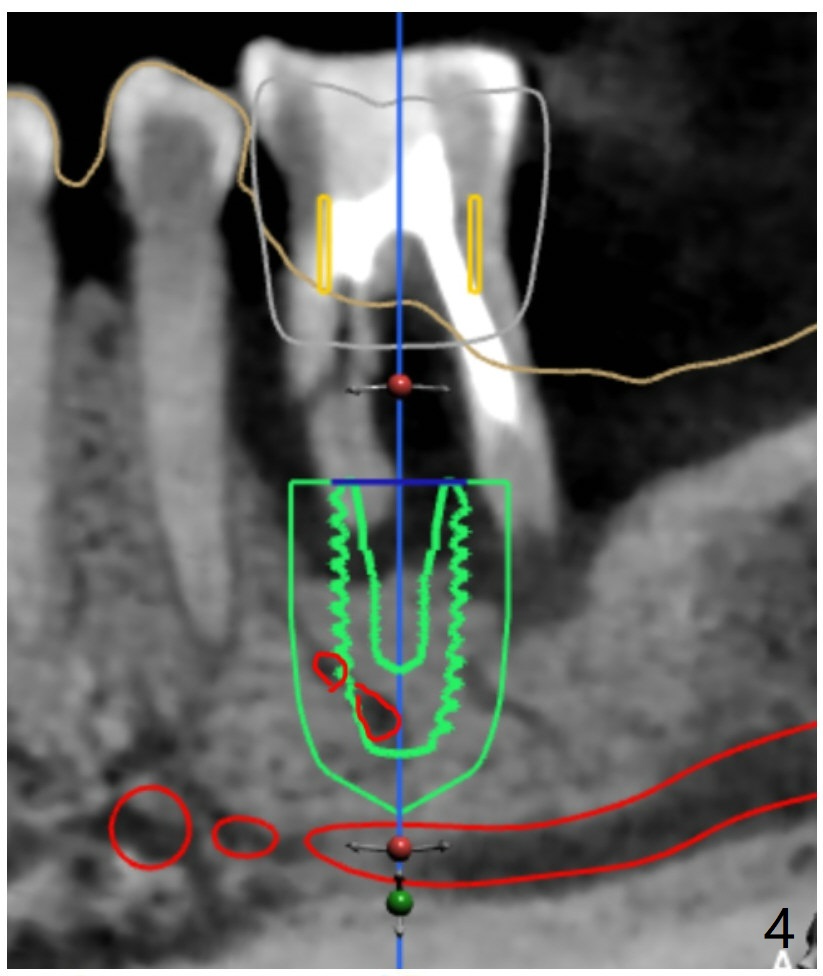

Placement M

When the patient finally agrees to have the tooth #19 to be extracted for implant (Fig.1), there is also mesial bone loss associated with mesial root fracture (Fig.2). To avoid truncation of the blood vessels toward the apex of the tooth #20 (Fig.2 black shadow and red line; Fig.4-6 (lab design) red symbols), a 5x10 mm implant will be placed more distal than the earlier design when the septum was present. The implant is also to be placed slightly higher than the native bone to improve crown/implant ratio; i.e., equical to the buccal, lingual and distal crests (Fig.3-6). Allograft will be placed in the gaps. After distal placement with minor axial change, new treatment plan is born. Return to Lower Molar Immediate Implant, Prevent Molar Periimplantitis (Protocols, Table), Trajectory, Weichat Xin Wei, DDS, PhD, MS 1st edition 01/14/2019, last revision 12/28/2019